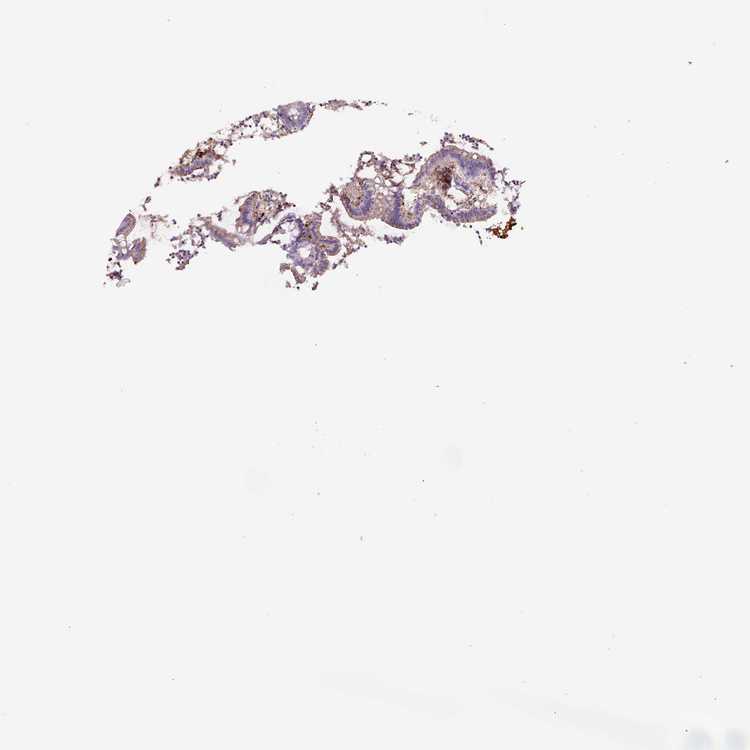

APPENDIX - Expression summary

Appendixi

On the top, protein expression in current human tissue, based on all annotated cell types, is reported with the units not detected (n), low (l), medium (m) and high (h). Underneath, protein expression in each annotated cell type are reported using the same units.

Protein expression data is based on knowledge-based annotation. For genes where more than one antibody has been used, a collective score is set.

APPENDIX - Antibody stainingi

Antibody staining in the annotated cell types in the current human tissue is reported as not detected, low, medium, or high, based on conventional immunohistochemistry profiling in selected tissues. This score is based on the combination of the staining intensity and fraction of stained cells.

Each image is clickable and will lead to virtual microscopy that enables deeper exploration of all samples and also displays staining intensity scores, fraction scores and subcellular localization as well as patient and tissue information for each sample.

Antibody HPA048982Antibody CAB000051Antibody CAB000066Antibody CAB072861Antibody CAB072862

Glandular cells Not detectedNot detectedNot detectedNot detectedNot detected

Lymphoid tissue MediumNot detectedMediumMediumNot detected